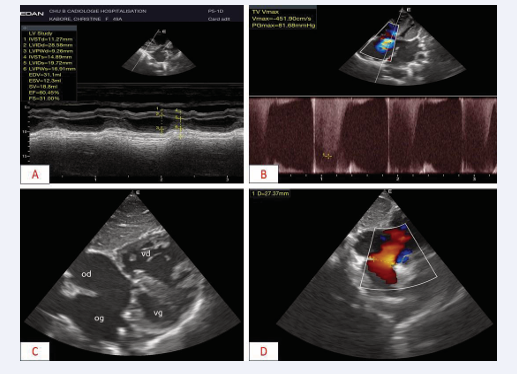

Transthoracic Doppler echocardiography revealed complex heart disease with mitral hypoplasia, a common atrioventricular canal and a single right ventricle (Figure 2).

Figure 2 Transthoracic Doppler echocardiography showing complex heart disease A: Para-sternal long-axis section, transventricular TM showing good systolic function B: Apical 4-cavity incidences, grade three Doppler IT with C & D: Subcostal 4-cavity view, complete atrioventricular canal, with single right ventricle

Figure 2: Transthoracic Doppler echocardiography showing complex heart disease A: Para-sternal long-axis section, transventricular TM showing good systolic function B: Apical 4-cavity incidences, grade three Doppler IT with C & D: Subcostal 4-cavity view, complete atrioventricular canal, with single right ventricle

There was also grade III pulmonary insufficiency with severe pulmonary hypertension (80 mmHg). Abdomino- pelvic angioscan revealed a patch of intra-parenchymal splenic hypodensity suggestive of an upper mid-polar splenic infarction measuring 39x33x36 (Figure 3); the other viscera were normal. Biological tests were normal.